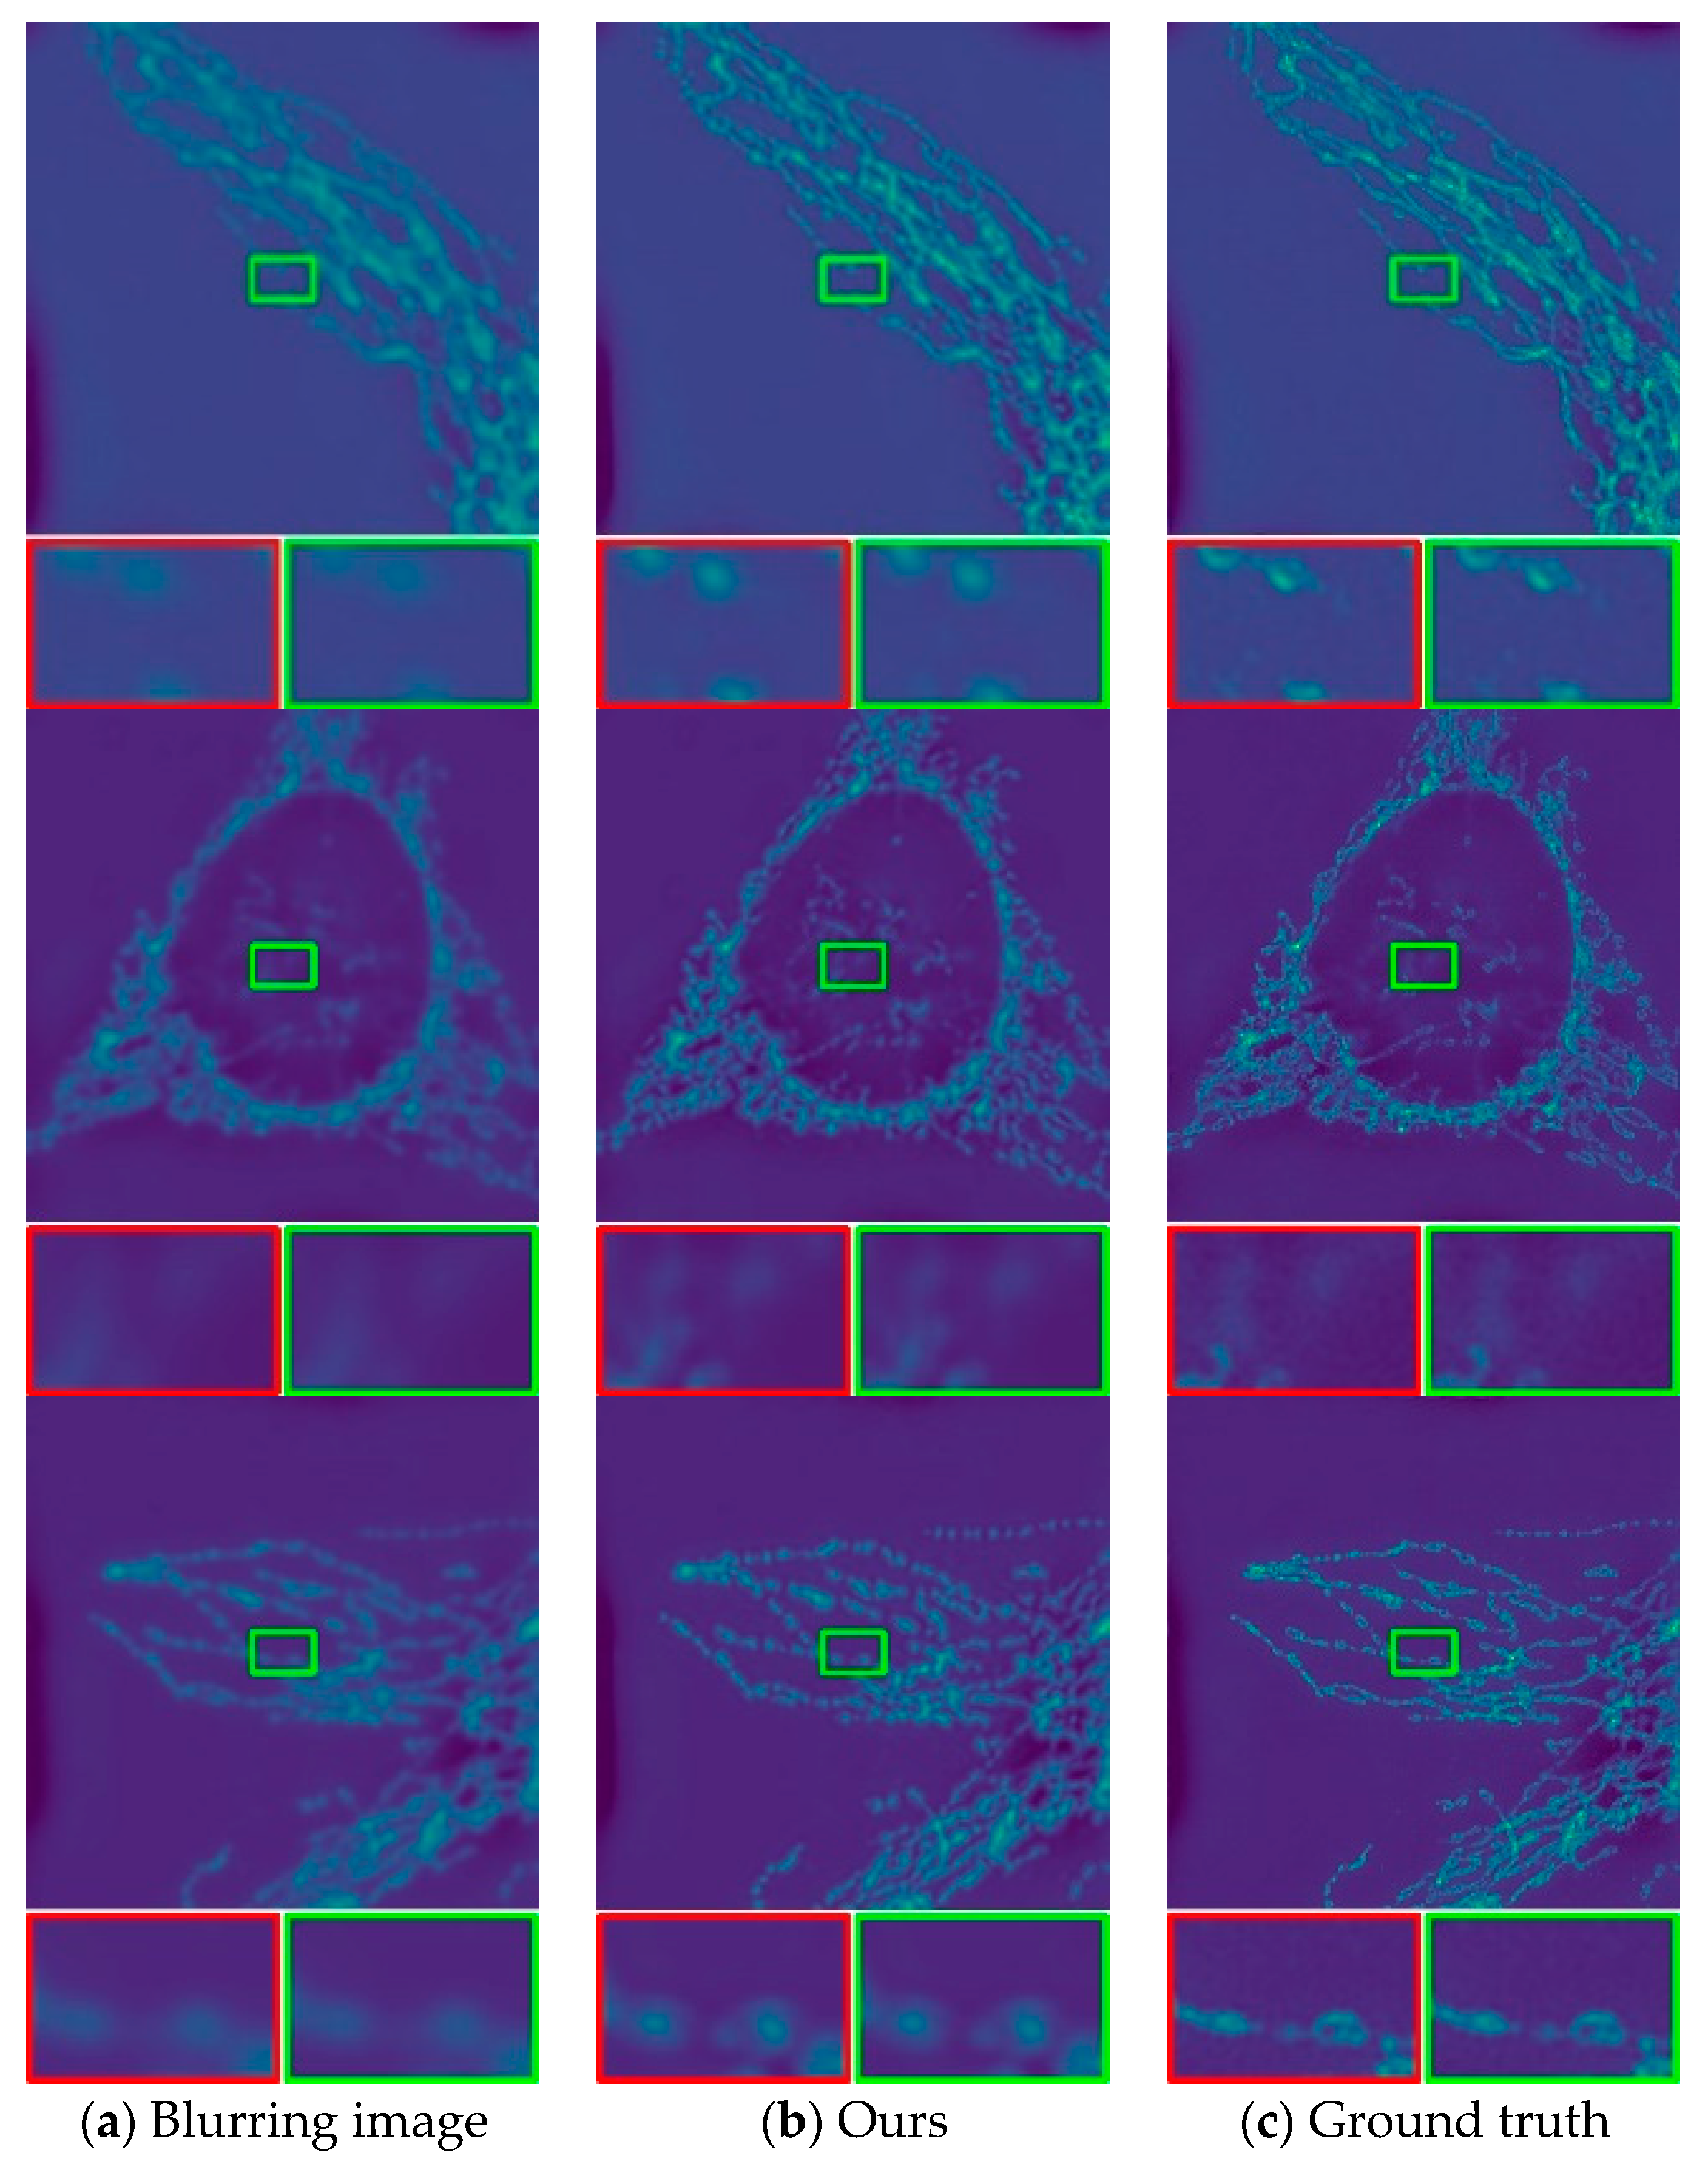

3.3. Evaluation on the Image Deblurring Network

3.4. Evaluate the Deblurring Effect on Real pCLE Images